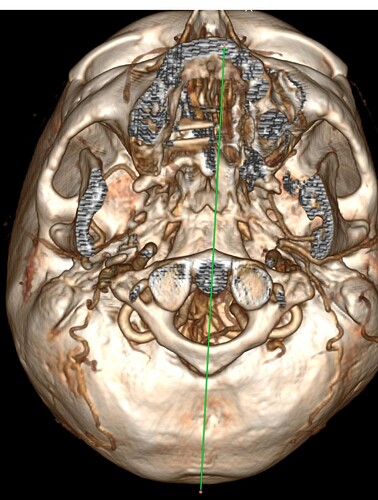

I have edited my post one more time, it must be my anxiety. I have added a picture of my scan with contrast. My elongated styloid processes are trapping my jugular vein. My carotid artery is off track… :scream:

@Hamela - Your styloids aren’t terribly long, but they are exceedingly thick, especially the left one which is a bit more angled than the right one. The right one is more curved. The thickness & angles of growth can significantly play into the symptoms & compression the styloids are causing.

I don’t know how significant it is that your right internal carotid artery is out of place even though Dr. Middleton made note of it, unless you’re also having symptoms related to your carotid artery which would be facial numbness, eye pain, neck pain, temporary visual loss or partial visual loss in one eye, dizziness, & headaches (these may differ somewhat from those caused by IJV compression). TIAs (mini strokes) are often also a symptom pointing to compression or irritation of the carotid artery(ies). It is possible your body has simply adapted to its new location w/o any problem.